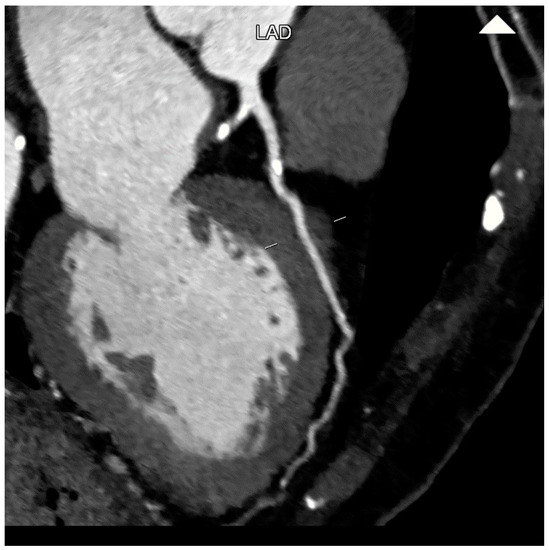

2. CCTA Imaging Protocol

3. Role of CCTA: Anatomical Evaluation